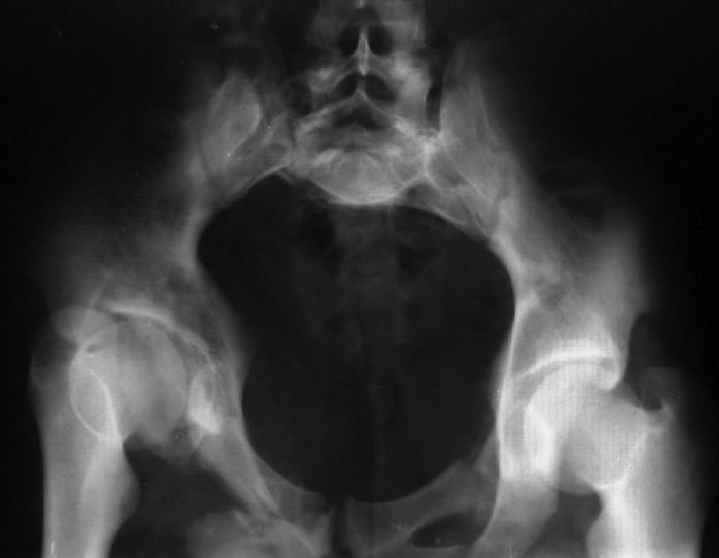

Для информации к размышлению о возможности исправления имеющейся деформации предлагаю похожий случай.